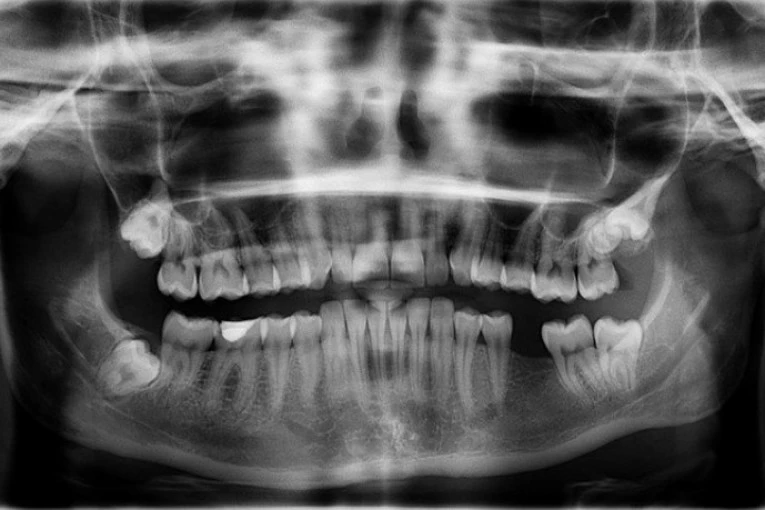

Foto: pixabay.comMajkl Šeridan bio je prinuđen da izvadi sve zube jer su bili potpuno uništeni. Pored toga, trpeo je jake bolove jer su u dodiru s bilo kakvom hranom užasno boleli.

Majklu je izvađeno svih 27 zuba koje je imao u vilici, a trenutno ima privremene proteze, nakon čega će mu zubar ugraditi implantate.